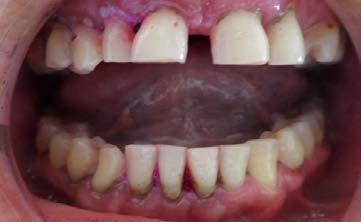

A 20 year-old male patient sought to a private practice with a chief complaint for discoloration and dull pain in maxillary anterior teeth region since 1 year. Clinical examination reveals non vital response of 11, 21. Radio graphically, maxillary left central incisor showed the radiolucency in the middle third of the root surface indicating of internal resoprtion (figure 1). The patient reports he did not remember trauma history in the same region. It was decided to complete the endodontic therapy for 11, 21.

After rubber dam isolation (Hygiene Dental Dam, Coltene Whaledent Germany) access cavity was initiated without local anesthesia as teeth were non vital. Working length was determined using apex locator (Root ZX II, Morita Tokyo, Japan) (figure 2). Biomechanical preparation was done using hand stainless steel file till 70K wrt 11 and 21 along with the copious irrigation with 5.25% sodium hypochlorite. An intracanal medicament dressing of calcium hydroxide was given and access opening was sealed with the cavit cement.